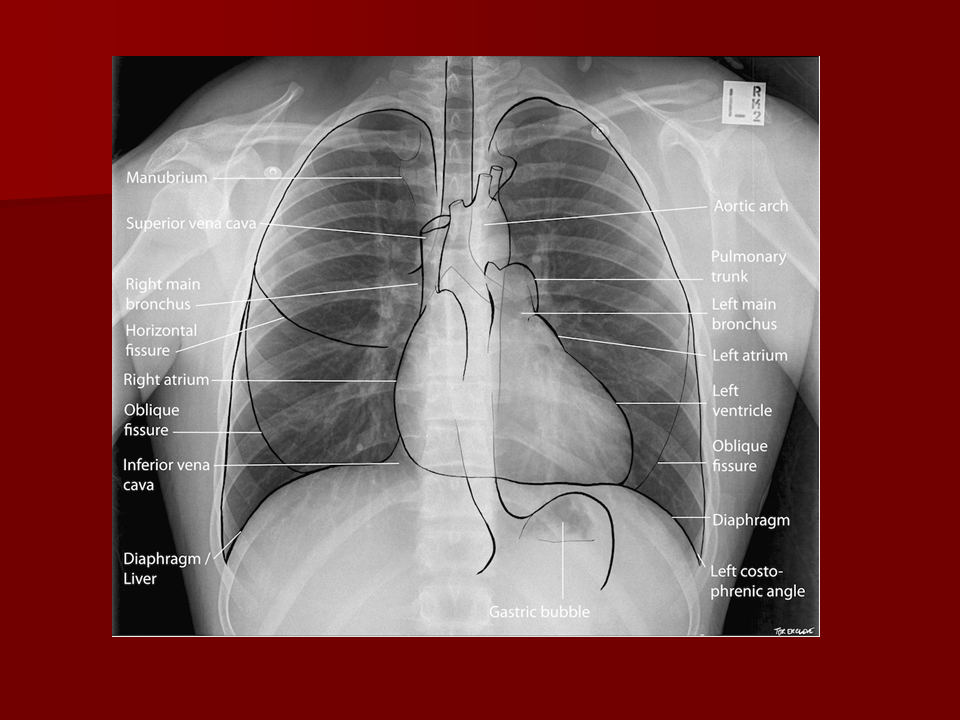

Chest X-ray anatomy